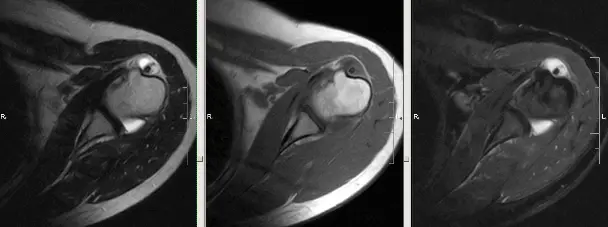

На зображенні: розрив сухожилля надостной м’язу.